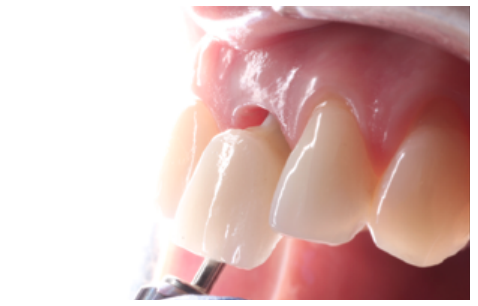

La fluorosis dental es una condición irreversible originada durante el desarrollo dental que genera pigmentaciones intrínsecas, alteraciones en el esmalte manifestadas a manera de manchas blancas, amarillas o marrones, que perjudican la estética y repercuten en el desenvolvimiento social. El presente reporte de caso clínico describe la combinación de los procedimientos de microabrasión y blanqueamiento dental, como alternativas en la eliminación de pigmentaciones dentales. Después del diagnóstico de la patología, verificación de ausencia de lesiones pulpares y caries, una explicación minuciosa a la paciente y obtención del consentimiento informado, se realizó limpieza de las superficies dentales y, bajo aislamiento absoluto, se procedió a realizar la técnica de microabrasión mediante ácido clorhídrico al 6,6% siguiendo las instrucciones del fabricante. Concluido el procedimiento y, observando que era posible mejorar aún más la estética, se decidió ejecutar el procedimiento de blanqueamiento dental, a base de peróxido de hidrógeno al 40% en el consultorio, seguido por peróxido de carbamida al 10% aplicado en el domicilio. Al finalizar el tratamiento se observó uniformidad en el color dental, conjugados con una evidente mejora en la calidad de vida y relación social de la paciente.